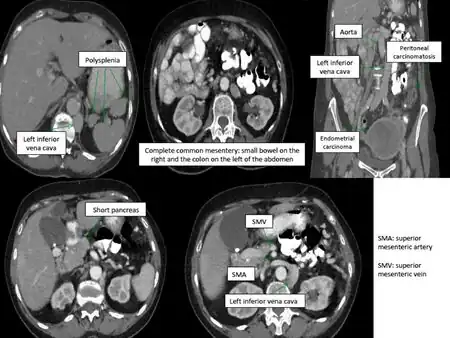

Situs ambiguus is a rare congenital defect in which the major visceral organs are distributed abnormally within the chest and abdomen. Clinically heterotaxy spectrum generally refers to any defect of Left-right asymmetry and arrangement of the visceral organs; however, classical heterotaxy requires multiple organs to be affected. This does not include the congenital defect situs inversus,[1] which results when arrangement of all the organs in the abdomen and chest are mirrored, so the positions are opposite the normal placement. Situs inversus is the mirror image of situs solitus, which is normal asymmetric distribution of the abdominothoracic visceral organs. Situs ambiguus can also be subdivided into left-isomerism and right isomerism based on the defects observed in the spleen, lungs and atria of the heart.

Abdominal organs, including the liver, stomach, intestinal tract, and spleen may be randomly arranged throughout the left-right axis of the body. Distribution of these organs largely dictates treatment, clinical outcomes, and further evaluation.

Random positioning of the stomach is often one of the first signals of situs ambiguus upon examination. Malrotation of the entire intestinal tract, or improper folding and bulging of the stomach and intestines, results in bowel obstruction. This impairment leads to vomiting, abdominal distension, mucus and blood in the stool. Patients may also experience abdominal pain. Intestinal malrotation is more commonly identified in patients with right atrial isomerism than in those with left atrial isomerism.

Isomeric patients often experience disruptions to splenic development during embryogenesis, resulting in an overall lack a spleen (asplenia) or development of many spleens (polysplenia). Asplenia is most often observed in patients with right atrial isomerism. Polysplenia results in 90% of patients with left atrial isomerism. Although they have many spleens, each is usually ineffective resulting in functional asplenia. Rarely, left atrial isomeric patients have a single, normal, functional spleen. Patients lacking a functional spleen are in danger of sepsis and must be monitored.[2]

- Deranged abdominal organ asymmetry:

- The stomach and spleen are prone to isolated reversal

- The stomach, liver, and a single adrenal gland are occasionally found in the midline.

- Vascular abnormalities:

- Interrupted inferior vena cava,

- Bilateral superior or inferior venae cavae

- Intrahepatic interruption of the inferior vena cava with connection to the azygos or hemiazygos veins

- Aberrant portal veins.